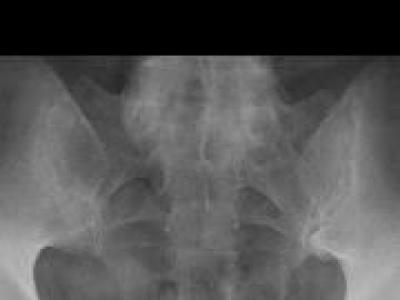

Pitfalls in sacroiliitis imaging: Bone marrow edema may also be seen in young-middle-aged postpartum women, & athlet

Pitfalls in sacroiliitis imaging: Bone marrow edema may also be seen in young-middle-aged postpartum women, & athletes & kids (ongoing bone growth) & w/ advancing age (DJD) https://t.co/bwS047wlmI https://t.co/FvWlEcZ5JP